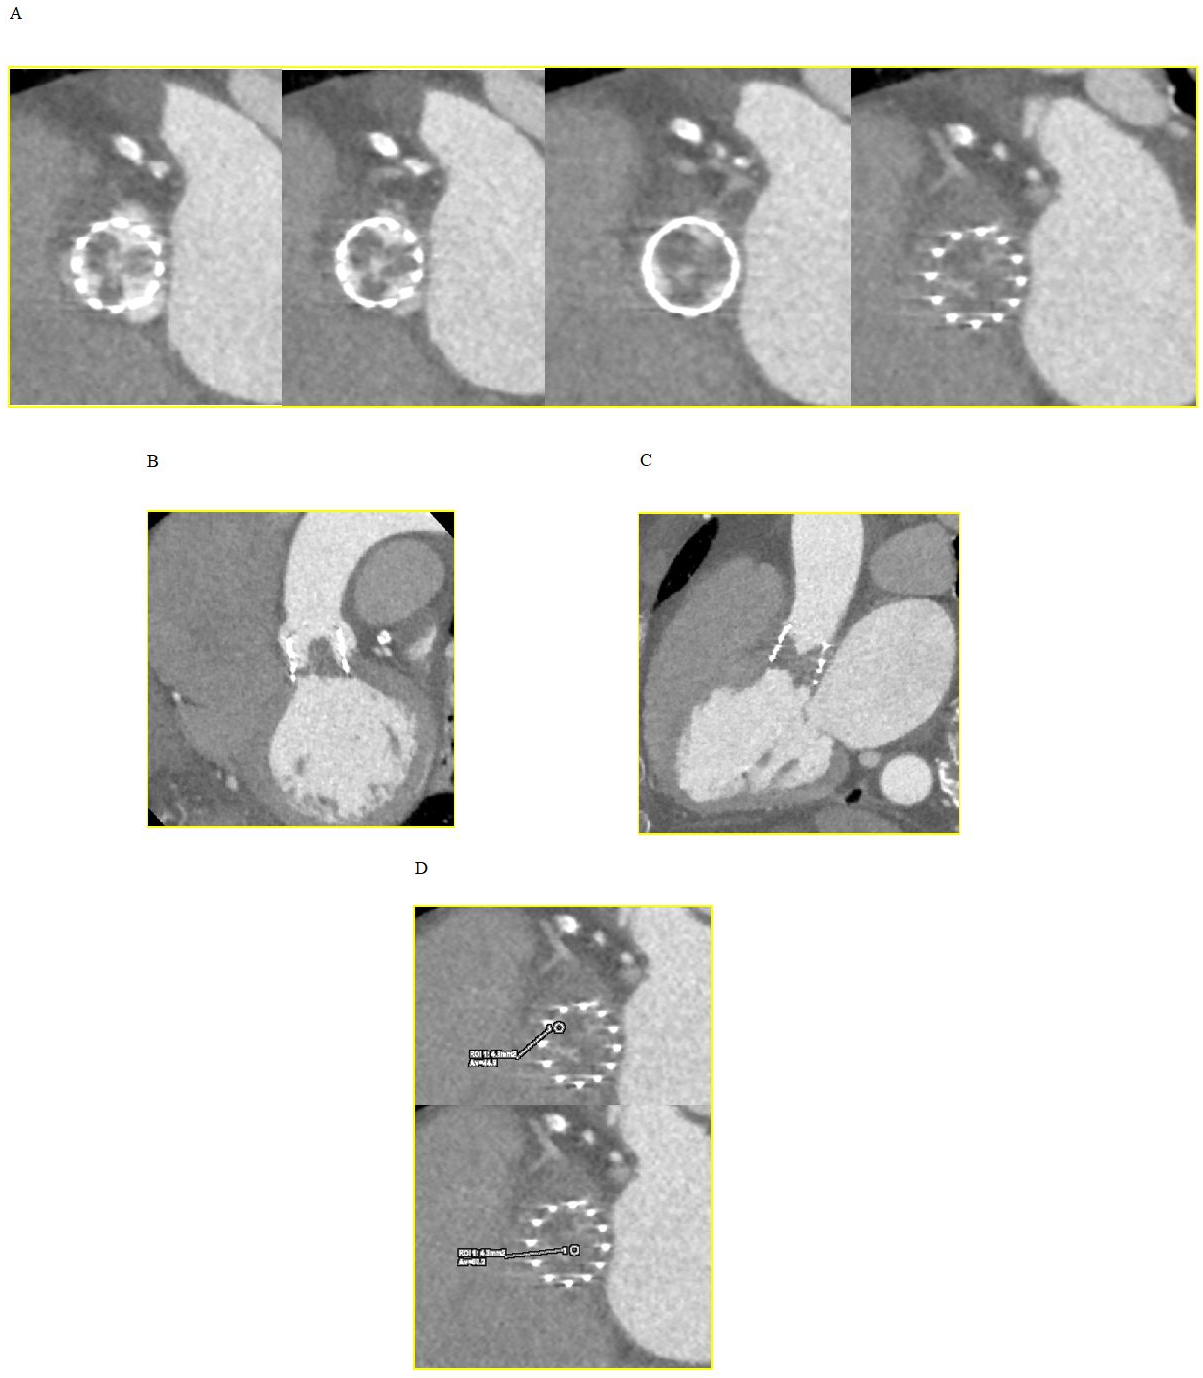

CT is not only crucial for the overall planning of TAVI, but can also be helpful in identifying specific factors that may be highly predictive of post-procedural thrombotic events: calcified tissue deposits or a bicuspid configuration that may alter the geometry and expansion of the TAVI, a particular composition of the damaged native valve that induces thrombosis due to exposure of tissue factor, and quantitative features of peri-aortic adipose tissue that are associated with an increased risk of LT [4] (Fig. 1).

Fig. 1.Native bicuspid valve experiencing TAVI thrombosis. (A) Axial view of the native valve showing bicuspid morphology with calcific raphe between the coronary cusps. (B) Axial, sagittal oblique and coronal oblique view of the transcatheter heart valve displaying post-procedural thrombosis of the non-coronary sinus. TAVI, transcatheter aortic valve implantation.